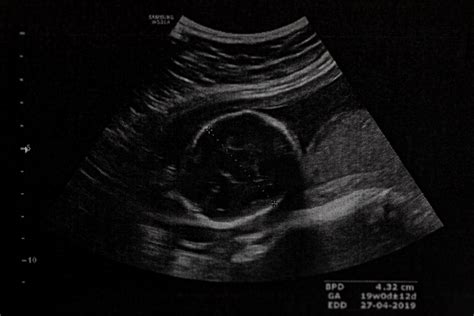

24. - 28. týždeň: Glukózový tolerančný test je skríningové vyšetrenie, ktoré slúži na včasné odhalenie gestačného diabetu (tehotenskej cukrovky), ktorý môže ohroziť mamičku aj dieťa. 20. - 22. týždeň: Podrobné ultrazvukové vyšetrenie plodu slúži na detekciu štrukturálnych a funkčných abnormalít, ktoré môžu byť typické aj pre chromozómové poruchy. Lekár detailne kontroluje mozog a lebečné štruktúry, tváričku - najmä oči, pery, nos, chrbticu a miechu, srdce, brušné orgány, končatiny, pohlavie. Ďalej sa kontroluje placenta a pupočník, plodová voda a rast a proporcie plodu.

Štandardné postupy zahŕňajú základné kontroly, ktoré sa vykonávajú pri plánovaných gynekologických prehliadkach. Výsledky sa zapisujú do vašej tehotenskej knižky. 24. - 28. týždeň: Glukózový tolerančný test je skríningové vyšetrenie, ktoré slúži na včasné odhalenie gestačného diabetu (tehotenskej cukrovky), ktorý môže ohroziť mamičku aj dieťa. 20. - 22. týždeň: Podrobné ultrazvukové vyšetrenie plodu slúži na detekciu štrukturálnych a funkčných abnormalít, ktoré môžu byť typické aj pre chromozómové poruchy. Lekár detailne kontroluje mozog a lebečné štruktúry, tváričku - najmä oči, pery, nos, chrbticu a miechu, srdce, brušné orgány, končatiny, pohlavie. Ďalej sa kontroluje placenta a pupočník, plodová voda a rast a proporcie plodu.